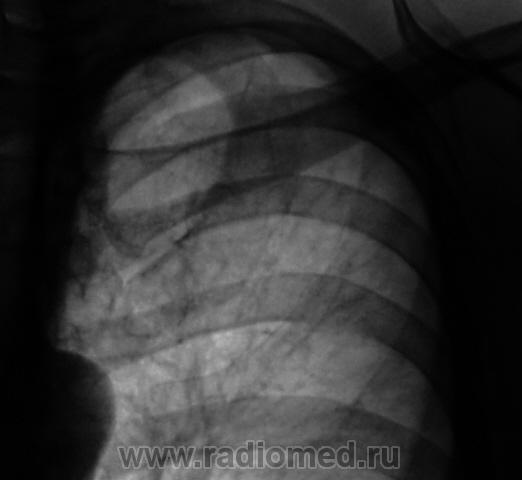

При расшифровке цифровых флюорограмм "пациент взят на контроль". Жалоб пациент не предъявляет. Произведено стандартное дообследование - рентгенография и томография.

Кальцинаты, инуративные очаги в зоне пневмосклероза. Отзвучавший туб. процесс. Больше пока не вижу.

Уважаемый Валентин Львович! Не стал бы торопиться с выводами об " отзвучавшем туберкулезном процессе". Во-первых, без наличия и изучения рентгенархива (при его наличии) делать такие выводы не осмелился бы. Во- вторых, зона пневмосклеротических изменений в легких не соответствует зоне очаговых изменений (гораздо больше!). Создается впечатление о наличии очагов отсева. В общем рентгенконтроль в динамике и консультация фтизиатра. Последнее слово за ними.

В таком случае, Валентин Львович, Вы подтвердили мои сомнения по поводу активности процесса. 2 года назад норма, а теперь такая картина. Это активный процесс. Выраженный пневмосклероз в виде "сетки" в целой доле. Пациента необходимо направить к фтизиатрам.